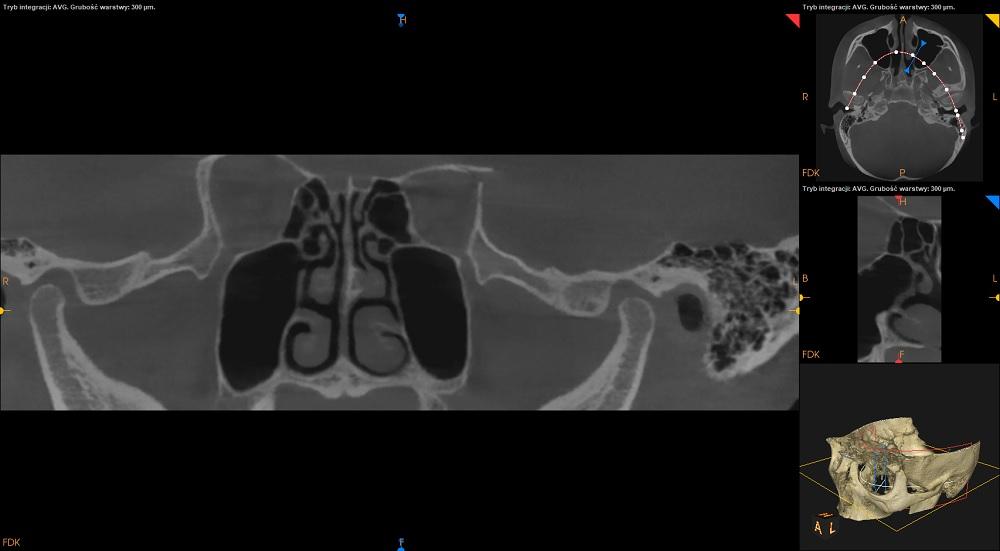

CBCT stawów skroniowo – żuchwowych w zwarciu

Strona prawa:

Badanie uwidoczniło nietypową budowę anatomiczną prawego kłykcia: bifid condyle- dwudzielny wyrostek to dość rzadka odmiana anatomiczna.

Widoczne wysunięcie kłykcia z panewki ku dołowi.

Najszersza górna część szpary stawowej.

Strona lewa:

Kłykieć o kształcie wypukłym ,obrys regularny, bez zmian.

Najszersza górna część szpary stawowej, przednia i tylna symetryczne.

Nie uwidoczniono zmian w budowie guzków i dołków stawowych.